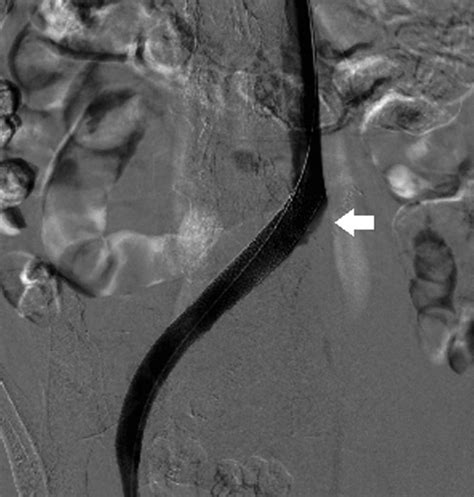

• Venography: A more invasive test that involves injecting a contrast dye into the veins to visualize blood flow.

• CT scan or MRI: To provide detailed images of the veins and surrounding structures.